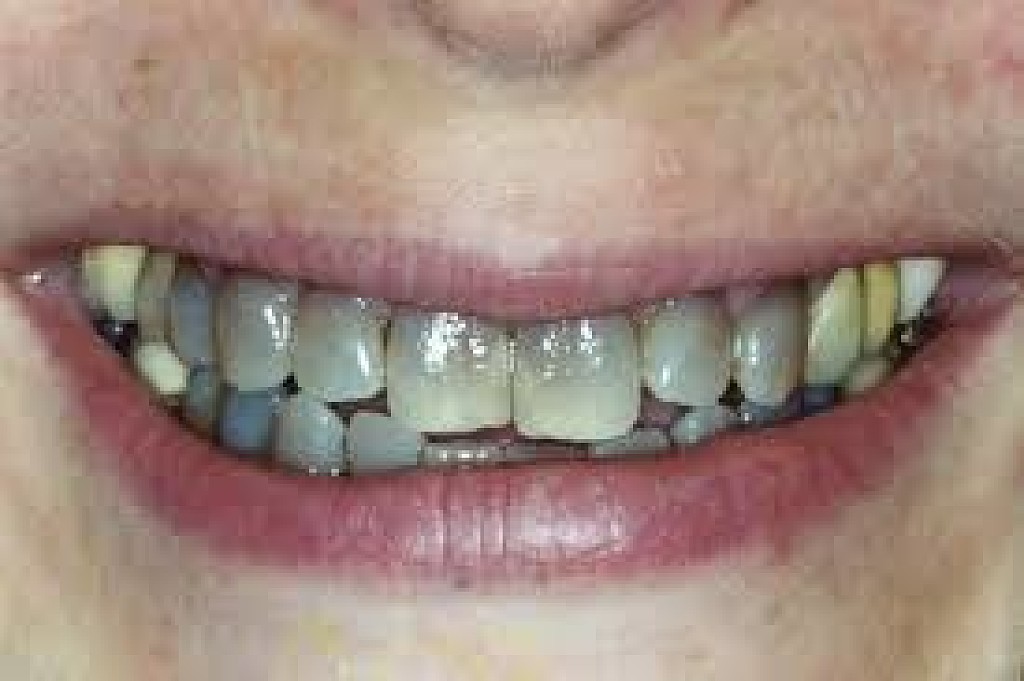

What Causes The Dark Line On My Gums?

You have seen smiles that you know have dental crowns in the front. You look at them and say to yourself that something is not natural. Many times, it is the dark rim of gum tissue that gives it away. The dark rim of gum tissue does not occur around natural teeth, only around teeth that have been covered with dental crowns.

The dark line is associated with an old porcelain dental crown. This style of dental crown is referred to as a porcelain fused-to-metal dental crown because it uses tooth-colored porcelain on the outside and it uses metal under the porcelain for strength. The dark line originates from the edge of the dental crowns where the porcelain and the metal meet at a knife-edge at the gum line. At the knife-edge, a very thin amount of the metal always shows. One of the illusionary techniques cosmetic dentists have used was to hide the thin dark line under the gum line. Over time, the gum tissue would recede and expose the dark line. In some patients the dark line would show through the gum and make it appear dark as well.

How Do You Get Rid of It?

The only way to eliminate the esthetic problem is to replace the dental crowns. When replacing just one single dental crown in the front, you should expect that it might take more than one try-in of the new dental crown before it is permanently cemented into place. Because your central incisors are the most prominent teeth in the mouth, matching them is the most difficult esthetic challenge. Only the best dental technicians are able to mimic one central incisor tooth next to another.

What Are Some of the Replacement Dental Crowns Like?

Some of the clever ways dentists and dental technicians have been able to mimic natural teeth is through the new advancements in dental materials. New all-tooth-colored ceramic dental crowns are the latest technological advancement cosmetic dentists have to recreate natural teeth. In comparison to porcelain fused-to-metal dental crowns, all-ceramic dental crowns do not contain any metal, thus no dark line can appear.